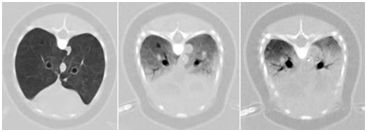

Cross sectional CT scan of the chest of a porpoise. Simulated depths of 0, 50, and 100m depth (left to right), showing the pressure related compression of lung tissue (air in the lung appears as the dark density).

A sophisticated CT (computer tomography) scanner is used to obtain high resolution mappings of the various aquatic animals, not just to determine cause of death, but also to understand how they survive in the ocean. Of special interest is understanding more on how echo location operates by studying the auditory anatomy. They are also studying how dolphins can dive deeply and surface quickly, normally without suffering from "the bends" - nitrogen bubbles in the blood stream.

The high resolution scans needed for these and other studies require precise positioning and movement of the animal being studied in a CAT scanner. For some studies, the deceased animal is suspended in water under various pressures to mimic dive gradients. This combination of the animal and the surrounding water can be on the order of 3100 lbs (1400 kg), much higher than the standard tables designed to position people within the scanner. Any positioning error, including vibrations, distort the images and may make the image less useful for resolving the questions of the investigation.